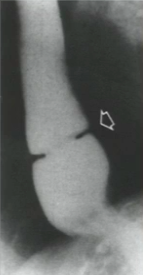

What causes this?

Weakness of muscular layer (cricopharyngeaus) in the esophagus that allows mucosa to protrude through and form a Zenker Diverticulum.

What type of diverticulum originates inferior to the cricopharyngeus?

Killian-Jaimeson Diverticulum